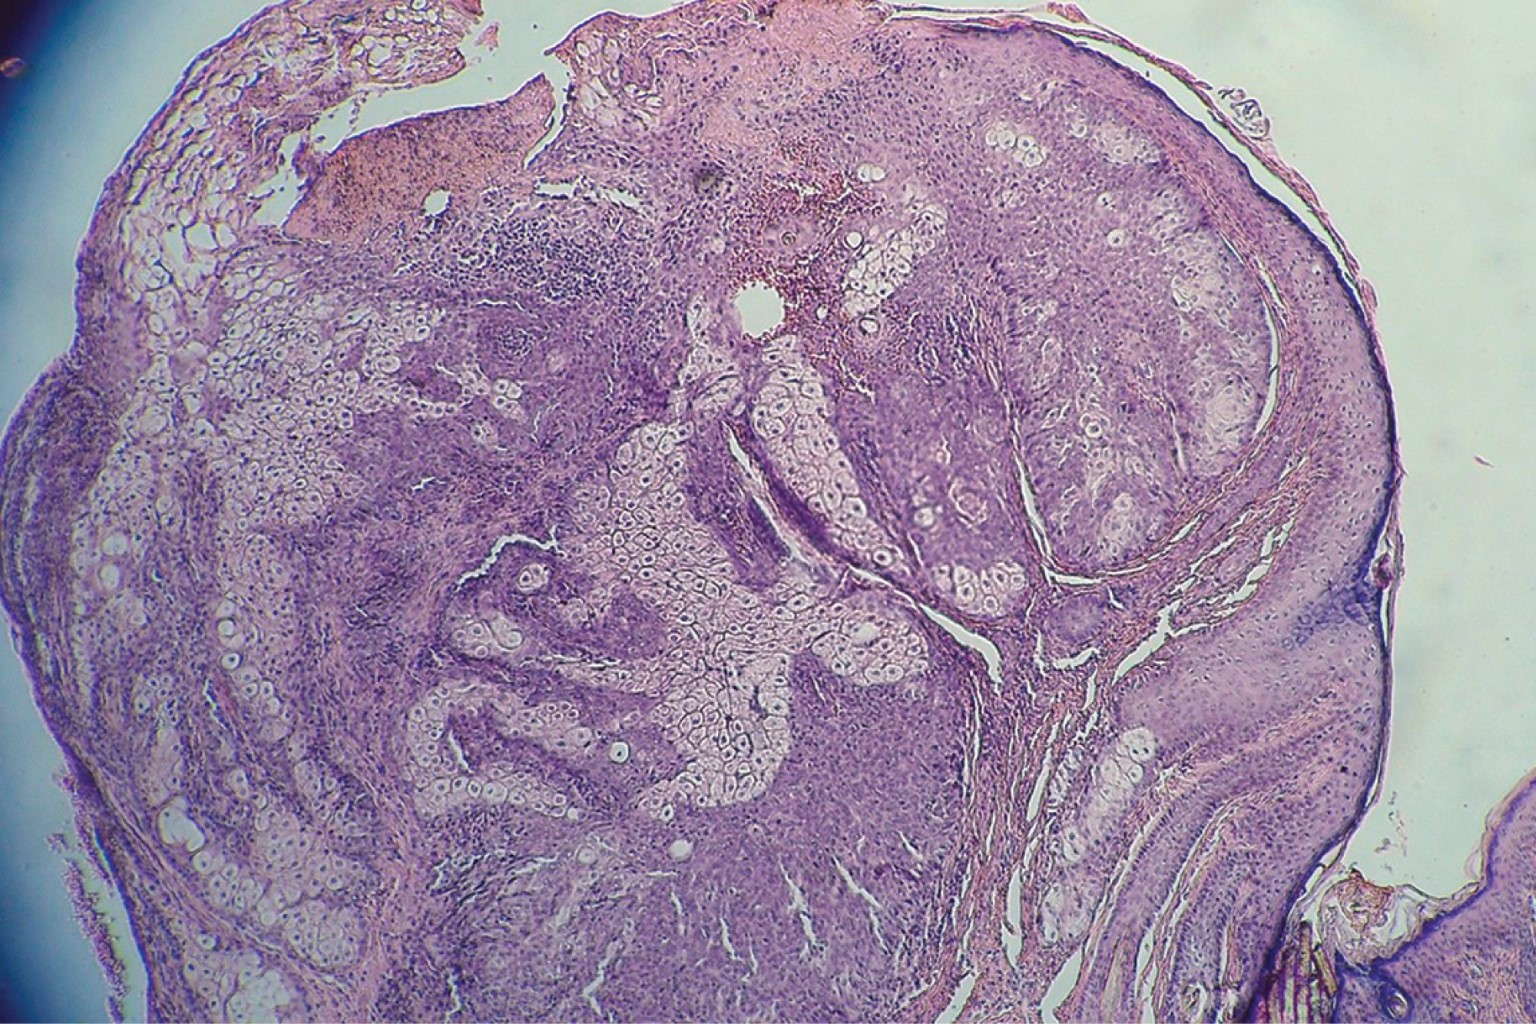

Se realiza biopsia incisional que reporta neoformación ligeramente exofítica cuya epidermis presenta escasa capa córnea y acantosis irregular moderada, por debajo de ésta se observan numerosos cordones de células basaloides que se entremezclan con tejido sebáceo maduro en proporciones iguales, rodeados por escasa reacción inflamatoria. Con lo anterior se integra el diagnóstico de sebaceoma (Figuras 6 y 7). En un segundo tiempo se realiza extirpación completa de la misma.

El estudio histopatológico establece el diagnóstico definitivo. Las características incluyen la presencia de una neoformación bien circunscrita que se asienta principalmente en dermis superficial, conformada por conglomerados de sebocitos inmaduros que se disponen en lóbulos de células basaloides indiferenciadas, poligonales, con escaso citoplasma que tiene núcleo de aspecto vesicular y nucléolo eosinofílico, que se intercalan con sebocitos maduros agrupados así como con ductos excretores bien diferenciados. Las definiciones actuales de sebaceoma enfatizan que el componente de células basaloides debe ser mayor de 50% para diferenciarlo del adenoma sebáceo; con todo, debido a que se trata de un criterio que se ha adoptado de manera arbitraria, algunos autores cuestionan su empleo.2,5 Otros hallazgos incluyen la presencia de focos de epitelio escamoso queratinizado, calcificaciones, áreas de diferenciación apocrina y alto índice de mitosis sin atipias celulares, lo que permite diferenciarlo del carcinoma sebáceo. Estos tumores pueden presentar diversos patrones de crecimiento que orientan al diagnóstico, entre los que se incluyen patrón ondulado, sinusoidal o laberíntico, y el similar a un patrón carcinoide.5